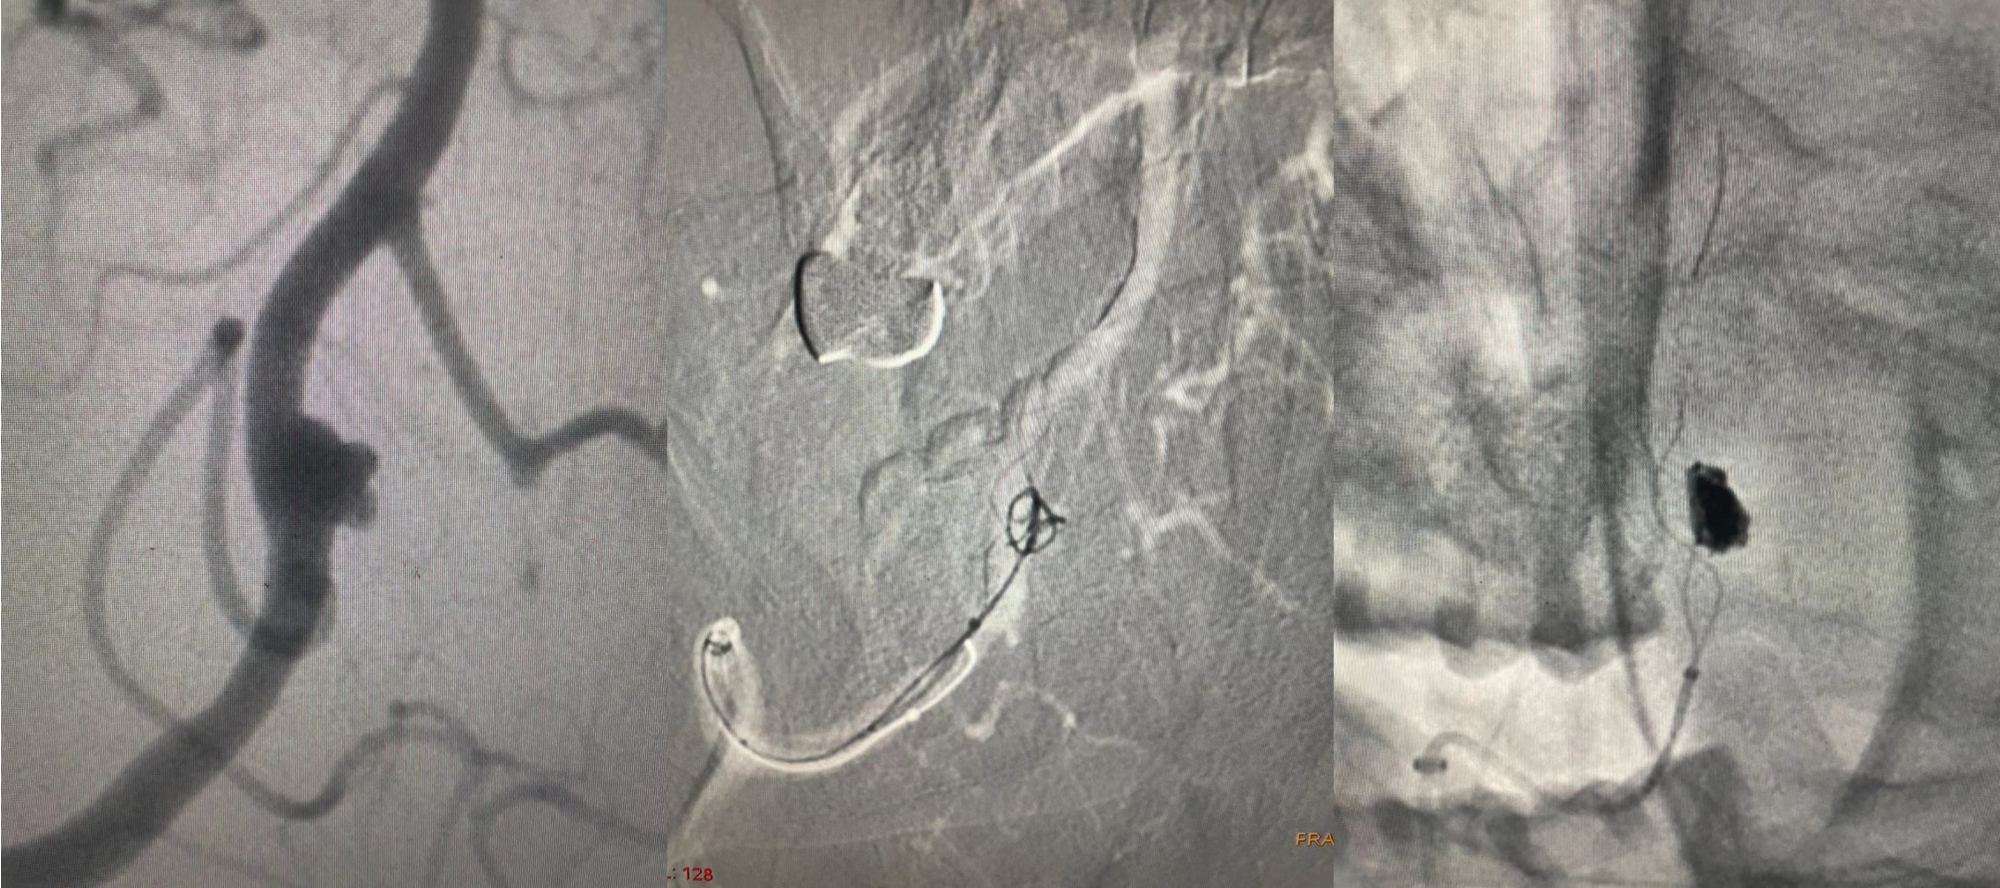

顱內動脈瘤的介入治療:支架輔助彈簧圈栓塞顱內動脈瘤